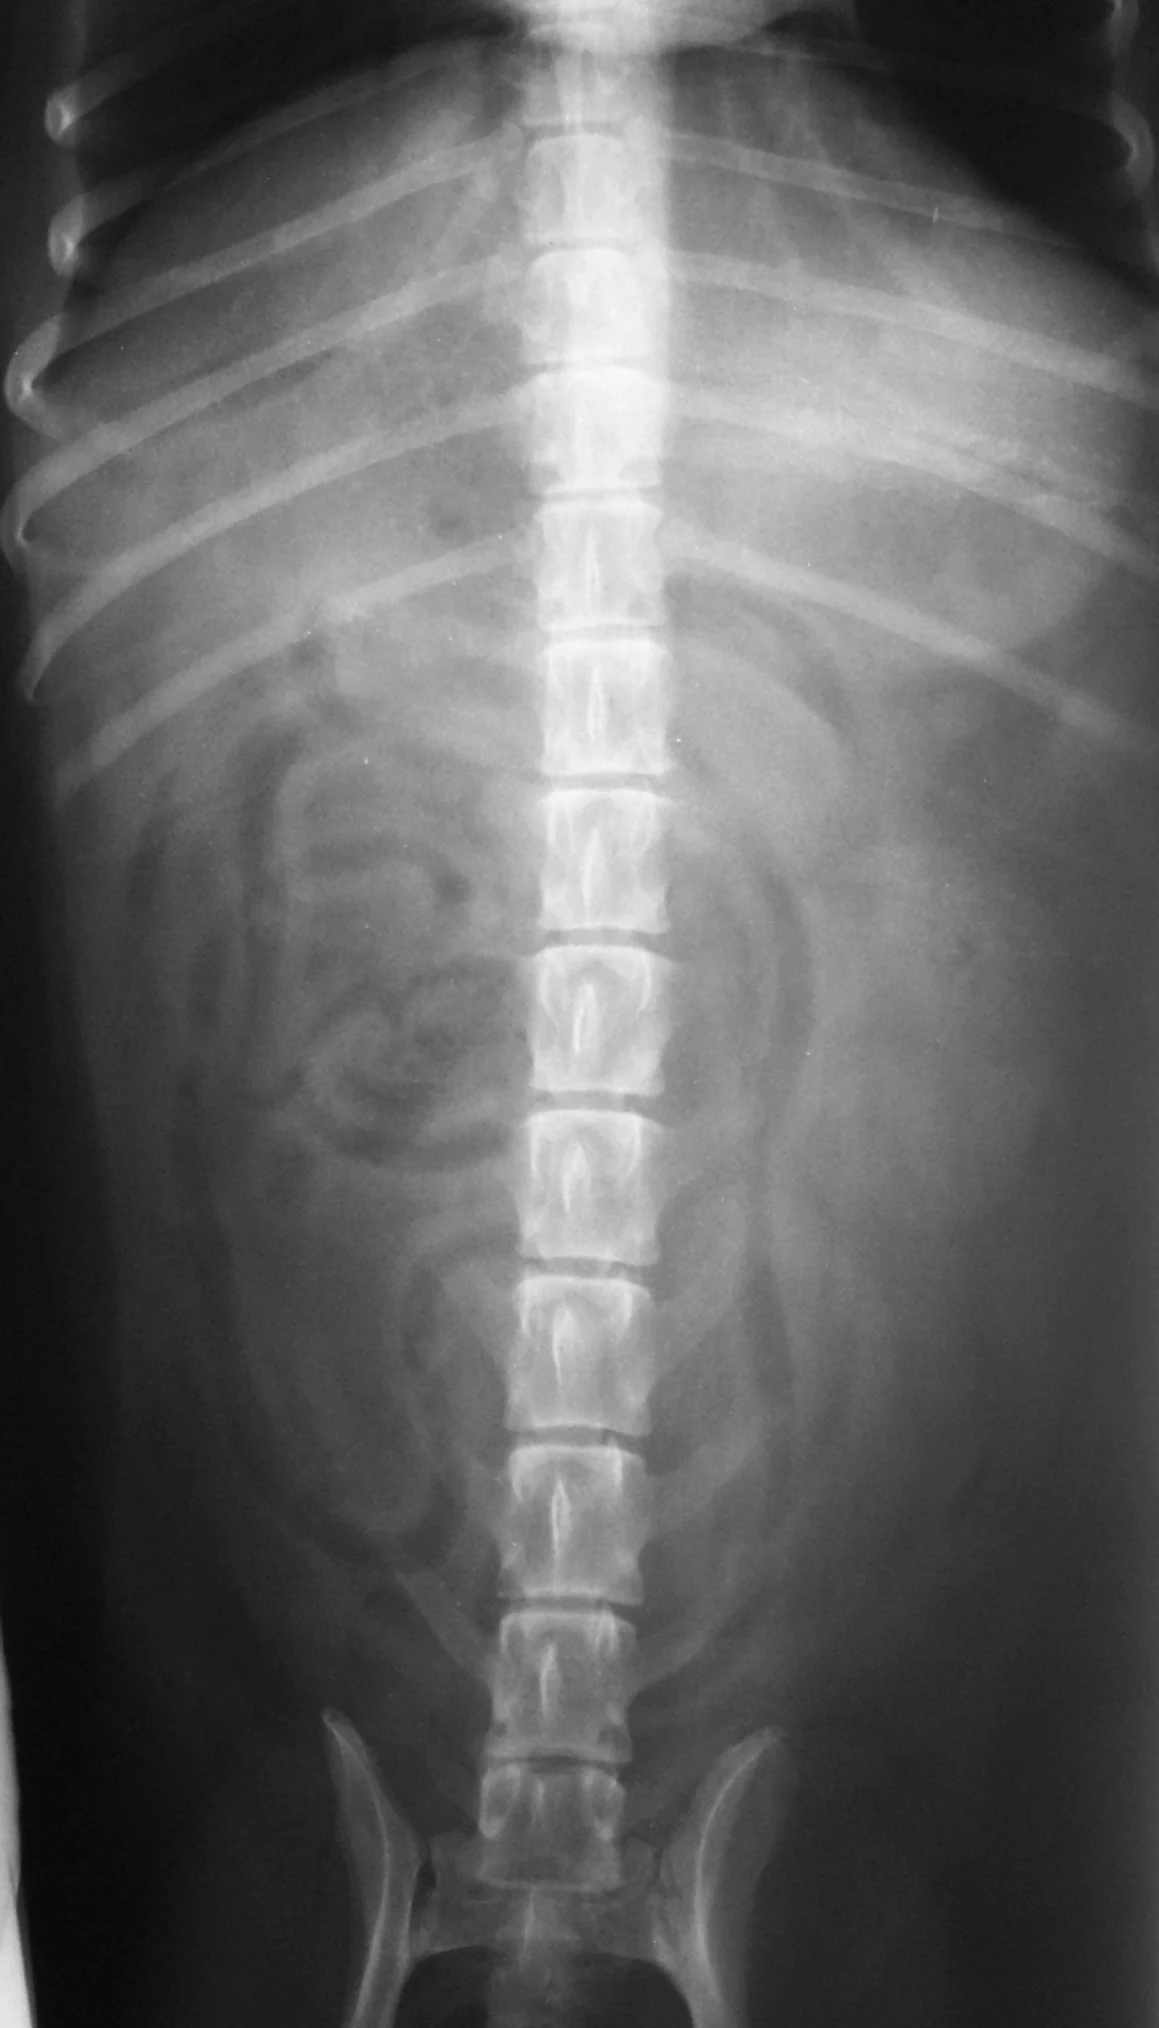

Gastroenteroscopy revealed a hard plastic foreign body (Figure 2) with curved, pointed ends. Points of the object were embedded in the gastric antral mucosa, resulting in hyperplasia. One of the curved points extended through the pylorus and hooked into the proximal duodenum (Figure 3). The endoscope could be passed around the foreign body into the duodenum, allowing biopsy of the duodenal mucosa. The gross appearance of the duodenal mucosa was normal (Figure 4). Attempts to remove the foreign body endoscopically were unsuccessful. Before the dog was sent to surgery for removal of the foreign body, colonoscopy was performed. The colon appeared normal on gross inspection (Figure 5). Biopsies were obtained from the cecum; ascending colon; transverse colon; and proximal, middle, and distal descending colon. At surgery, a gastrotomy incision was made in the pyloric antrum and the foreign body was forcefully removed. It was a plastic object used to secure the legs of a turkey carcass.

Endoscopy of the gastric antrum showing the foreign body and the mucosal proliferation induced by its presence

Endoscopy of one end of the foreign body hooked around the pylorus